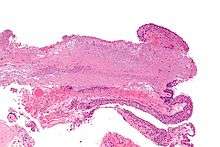

Pathology

Pterygium in the conjunctiva is characterized by elastotic degeneration of collagen (actinic elastosis[6]) and fibrovascular proliferation. It has an advancing portion called the head of the pterygium, which is connected to the main body of the pterygium by the neck. Sometimes a line of iron deposition can be seen adjacent to the head of the pterygium called Stocker's line. The location of the line can give an indication of the pattern of growth.

The exact cause is unknown, but it is associated with excessive exposure to wind, sunlight, or sand. Therefore, it is more likely to occur in populations that inhabit the areas near the equator, as well as windy locations. In addition, pterygia are twice as likely to occur in men than women. Some research also suggests a genetic predisposition due to an expression of vimentin, which indicates cellular migration by the keratoblasts embryological development, which are the cells that give rise to the layers of the cornea. Supporting this fact is the congenital pterygium, in which pterygium is seen in infants.[7] These cells also exhibit an increased P53 expression likely due to a deficit in the tumor suppressor gene. These indications give the impression of a migrating limbus because the cellular origin of the pterygium is actually initiated by the limbal epithelium.[8]

The pterygium is composed of several segments:

- Fuchs' Patches (minute gray blemishes that disperse near the pterygium head)

- Stocker's Line (a brownish line composed of iron deposits)

- Hood (fibrous nonvascular portion of the pterygium)

- Head (apex of the pterygium, typically raised and highly vascular)

- Body (fleshy elevated portion congested with tortuous vessels)

- Superior Edge (upper edge of the triangular or wing-shaped portion of the pterygium)

- Inferior Edge (lower edge of the triangular or wing-shaped portion of the pterygium).